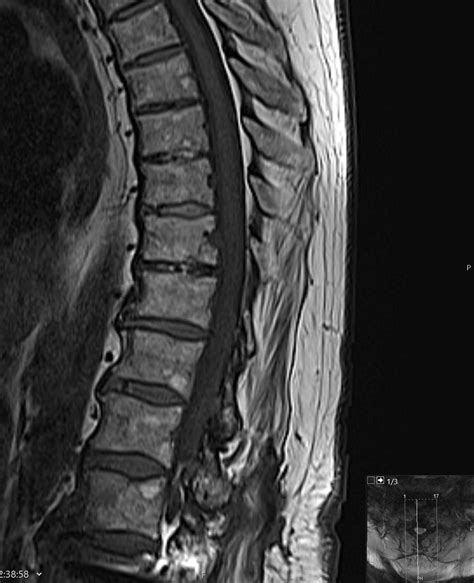

• Imaging Tests: X-rays, CT scans, and MRI scans to visualize the spine and identify the presence of osteophytes and disc degeneration.